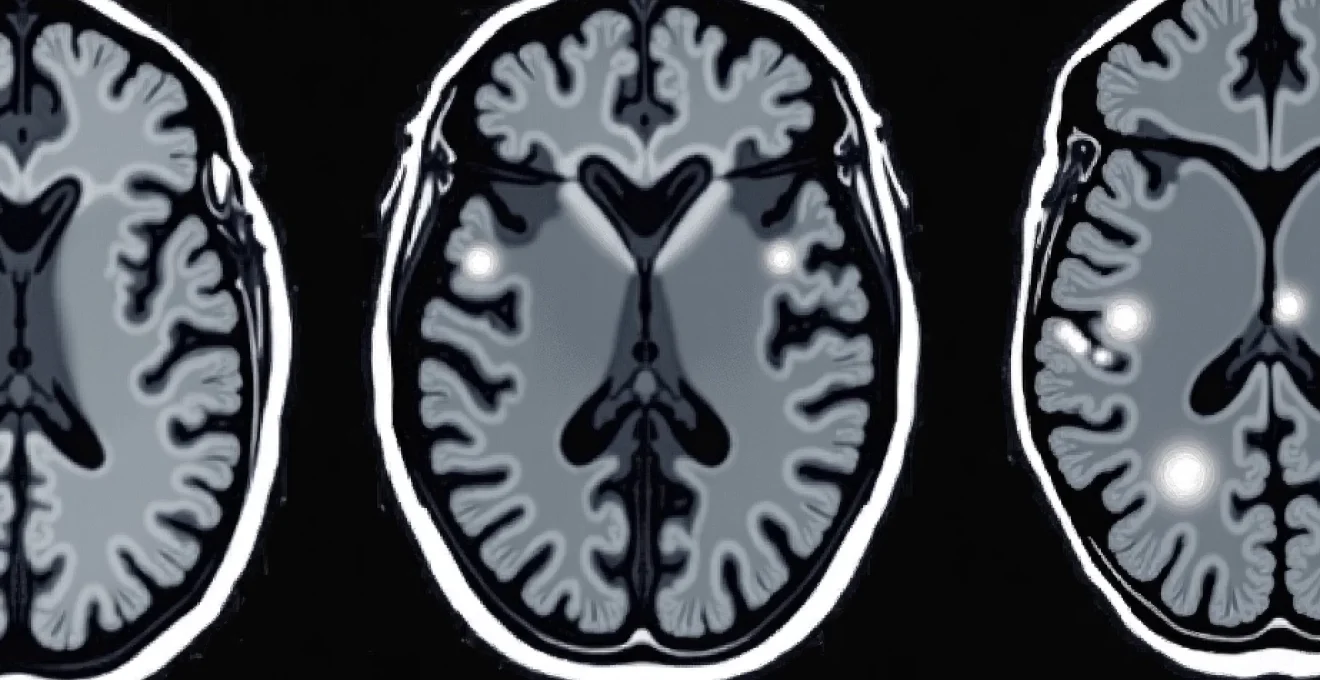

White spots appearing on brain MRI scans represent one of the most frequently encountered radiological findings in modern neuroimaging, yet they can cause considerable anxiety for patients and present diagnostic challenges for clinicians. These hyperintense signals, technically known as white matter hyperintensities, appear as bright areas on specific MRI sequences and can indicate a wide spectrum of conditions ranging from normal ageing changes to serious neurological diseases. Understanding the clinical significance of these findings requires careful analysis of their location, pattern, and association with patient symptoms and medical history.

The interpretation of white matter lesions has evolved significantly with advances in MRI technology, allowing radiologists to detect increasingly subtle changes in brain tissue. However, this enhanced sensitivity has also highlighted the complexity of distinguishing between benign age-related changes and pathological processes that require medical intervention. The presence of white spots on brain MRI doesn’t automatically indicate disease, but their characteristics can provide valuable insights into underlying vascular health, inflammatory conditions, and neurodegenerative processes.

White matter hyperintensities manifest as bright signal abnormalities on T2-weighted and fluid-attenuated inversion recovery (FLAIR) MRI sequences. These imaging techniques are particularly sensitive to changes in tissue water content and can detect subtle alterations in brain microstructure that may not be visible on other sequences. The appearance of these lesions reflects disruption of normal tissue architecture, often involving damage to myelin sheaths, axonal integrity, or changes in tissue hydration.

FLAIR sequences prove particularly valuable for detecting periventricular white matter changes because they suppress the bright signal from cerebrospinal fluid, allowing better visualisation of lesions adjacent to the ventricular system. Modern 3T MRI scanners can achieve submillimetre resolution, enabling detection of lesions as small as 2-3 millimetres in diameter. The technical parameters used, including echo time, repetition time, and slice thickness, significantly influence lesion conspicuity and detection sensitivity.